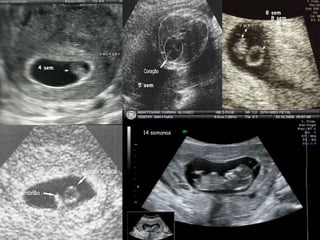

c) Diagnóstico Ultrassonografico

4 sem

5 sem

8 sem

14 semanas